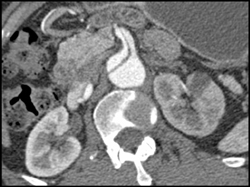

Aortic Aneurysm With VRT and MIP. IMA Only Seen With VRT